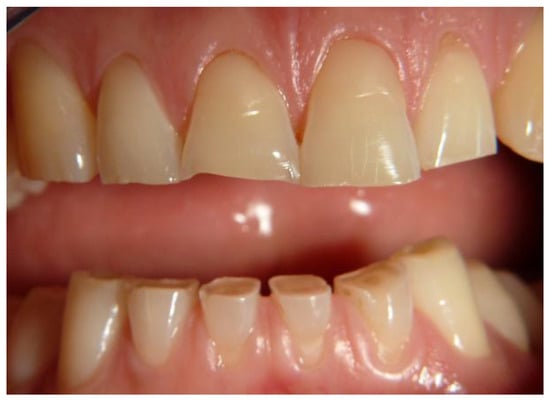

Following this classification we observed: Score 1 (loss of enamel characteristics) in four CD patients, Score 2 (exposing dentine for less than one-third of surface) in three, Score 3 (exposing dentine for more than one-third of surface) in two (Figure 3). In the control group, we only found three patients with tooth wear, all classified as Score 1.

Figure 3. A case of tooth wear in a celiac disease (CD) patient (Score 3).